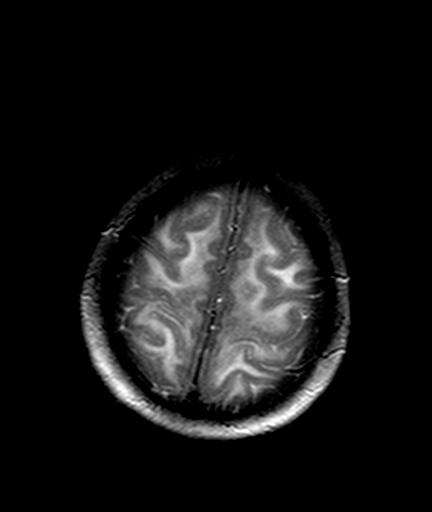

发热、头痛伴精神异常1周

较对称性脑白质异常信号,深部白质t2明显低信号(铁质沉积过多?)

考虑脑白质病变,请结合临床病史及实验室检查进一步分析。

f 23岁